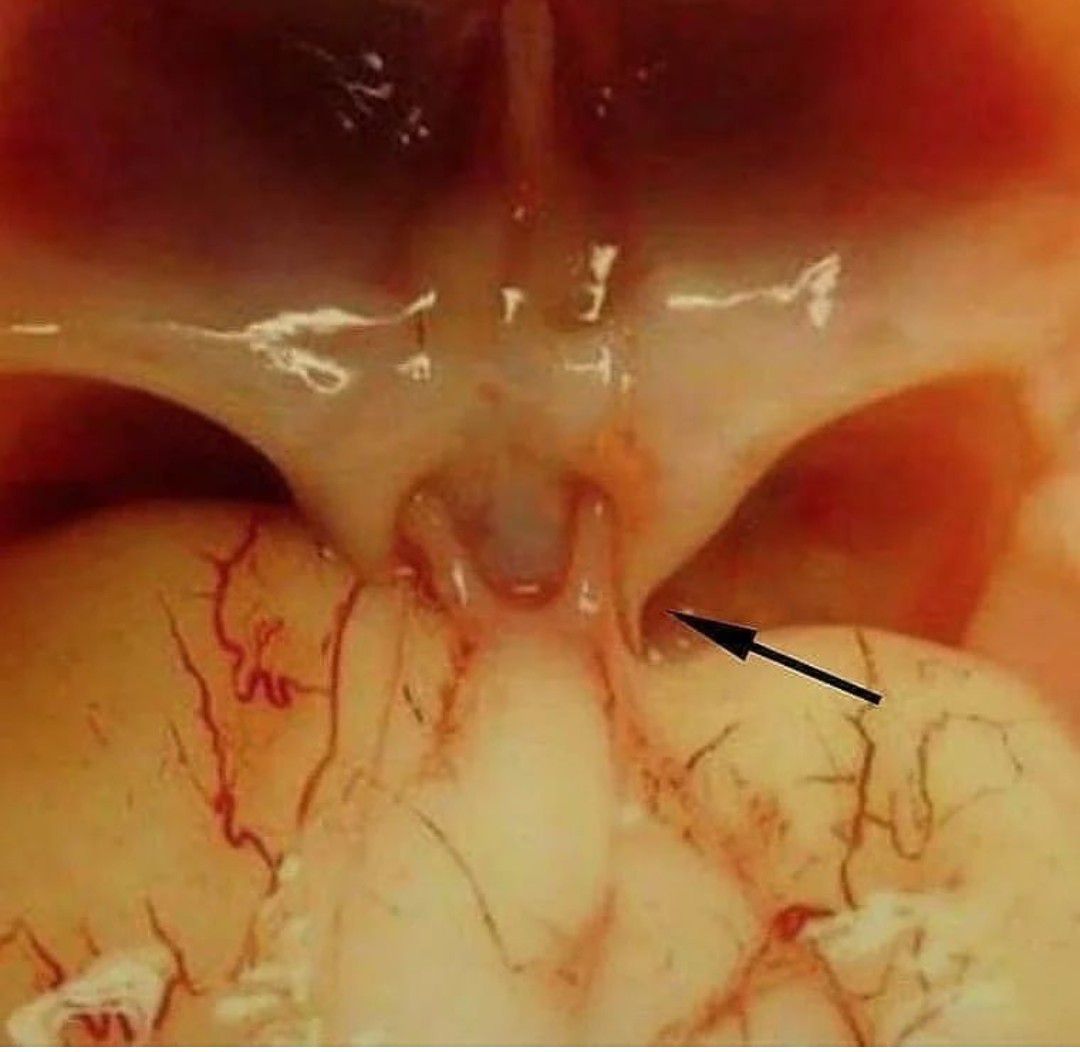

Optic Chiasm

The place in the brain where some of the optic nerve fibers coming from one eye cross optic nerve fibers from the other eye.